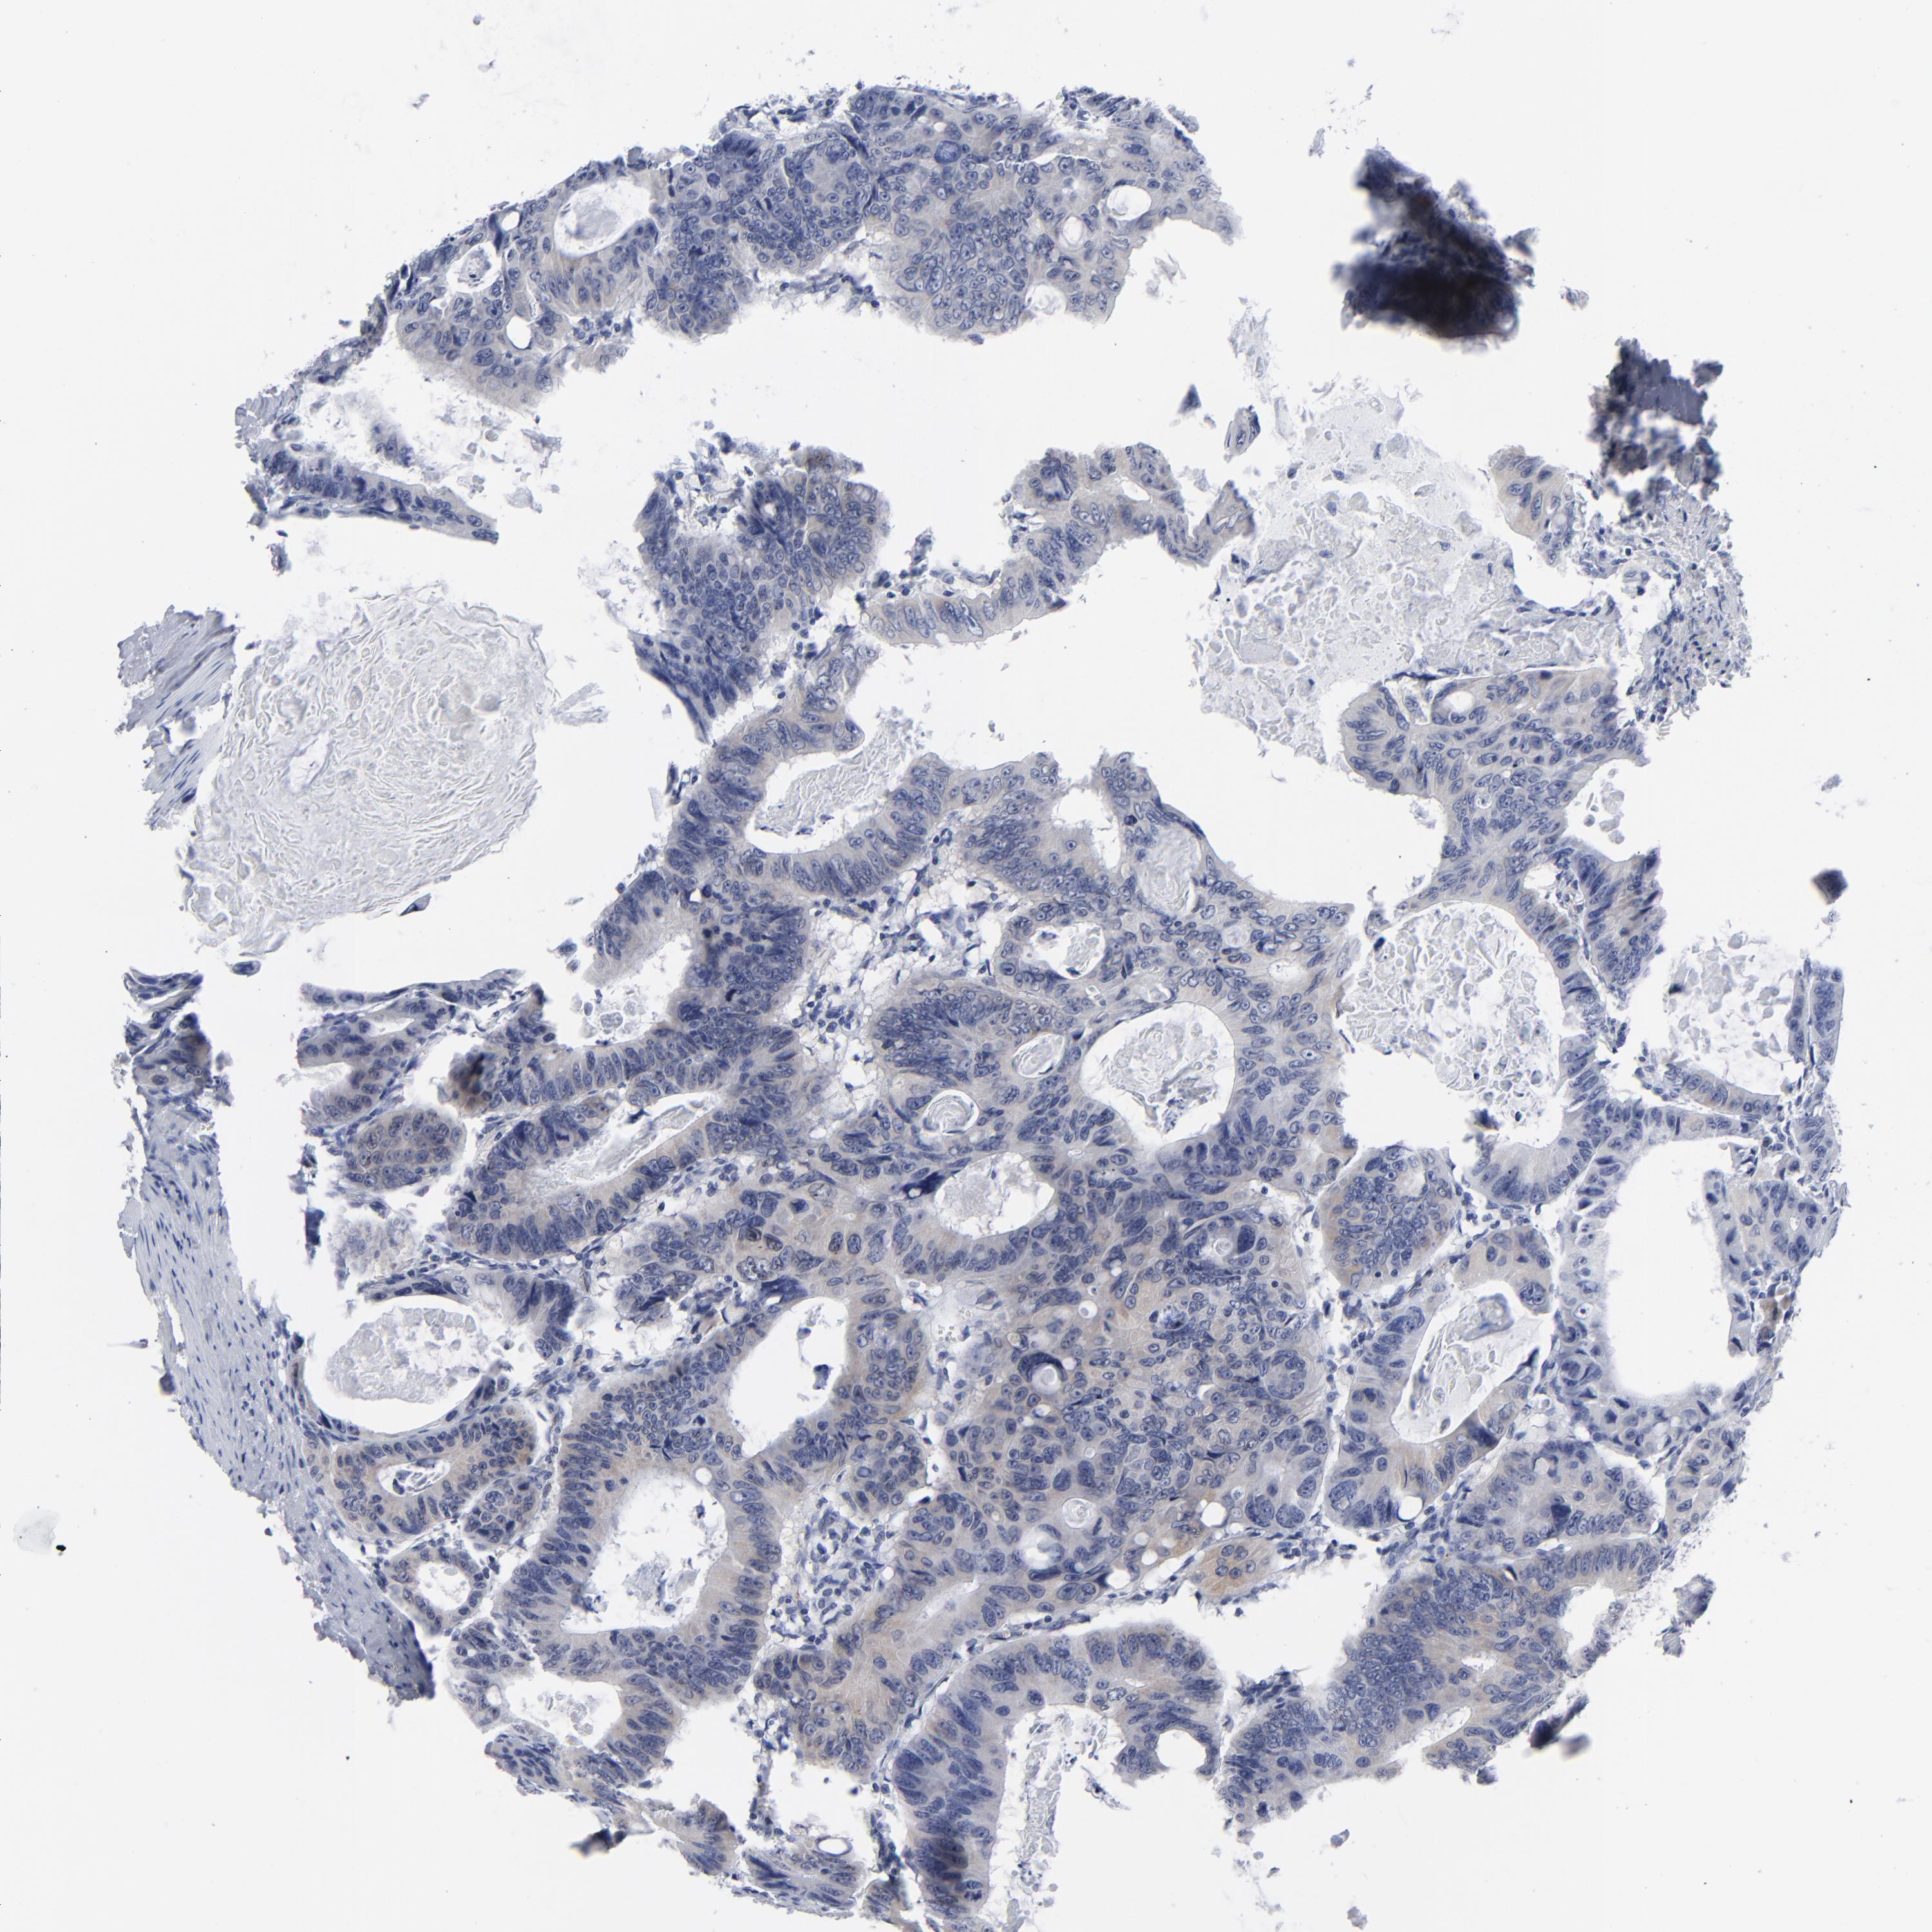

CANCER COLORECTAL CANCER Show tissue menu

Colorectal cancer

Human cancer

Colon adenocarcinoma